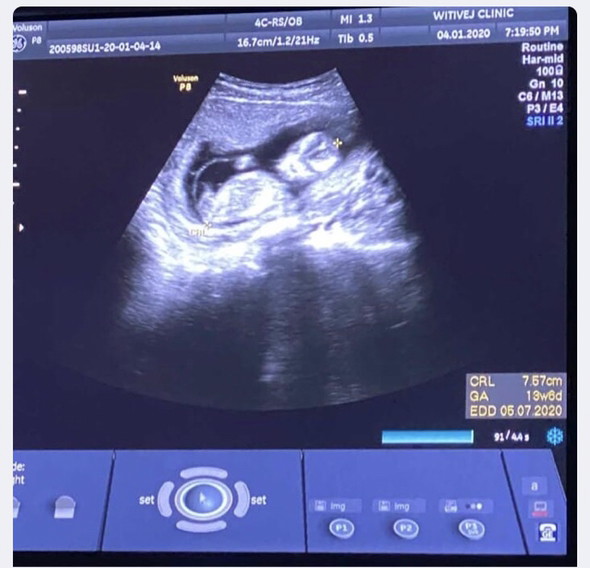

แม่ๆค่ะ 3เดือนนี่ลูกเริ่มเป็นตัวอ่อนๆหรือยังค่ะ อยากทราบค่ะ

น้องมีแขน มีขา มีอวัยวะครบแล้วค่ะ